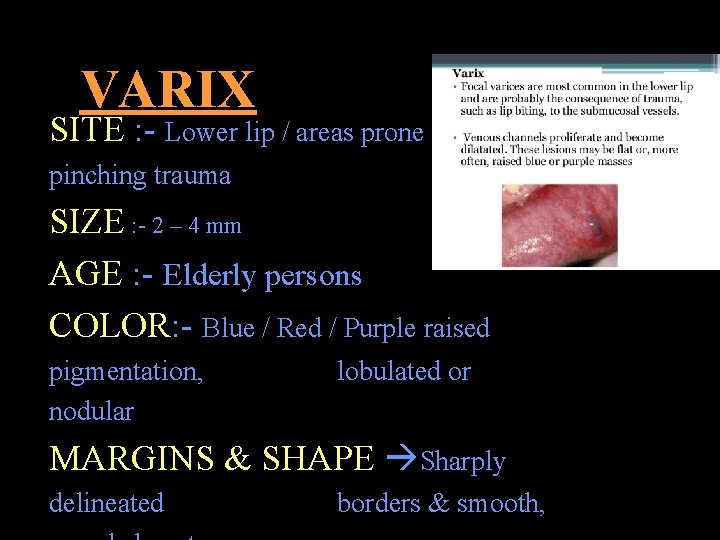

VARIX AND VARICES DISTENDED VEIN RESULT FROM PARTIAL BLOCKAGE OF VEIN • VARICES / VARICOSITY Pathological dilatation of vein or venules • VARIX Focal dilatation of group of venules or vein

VARIX SITE : - Lower lip / areas prone to pinching trauma SIZE : - 2 – 4 mm AGE : - Elderly persons COLOR: - Blue / Red / Purple raised pigmentation, nodular lobulated or MARGINS & SHAPE Sharply delineated borders & smooth,